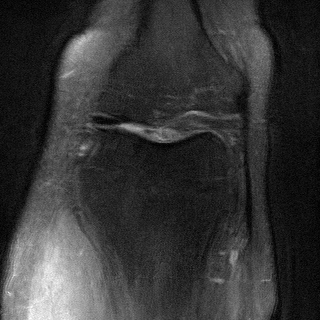

MRI with multi-contrast side information: We use fastMRI knee dataset (Zbontar et al., 2018) with the ContextMRI model (Chung et al., 2025). We pair PD and PDFS contrasts, reconstructing one from the other under undersampling with 2% ACS. We use normalized mutual information (NMI) as reward, which is robust to contrast changes. Fig. 6 highlights sharper edges and more faithful structure. Table 10 in Appendix D.3 shows our methods consistently improves the baseline in all the metrics of interest.

We used the contrast-pairings among the files in the fastMRI dataset, provided by (Atalık et al., 2025). We collect the data from the (fastMRI) source and preprocess to be compatible with the inputs in ContextMRI. Specifically, the setup used in the data is multi-coil MRI acquisition, which requires us to estimate the coil sensitivity maps, and then a complex reconstruction from them. ContextMRI takes complex values as inputs and denoises to produce a complex-valued 2D image. We computed NMI with bins at each step of the diffusion process to balance complexity with performance. We use the defaults parameters as in ContextMRI, except for the acceleration factor, and the center fraction (ACS), . We use a pair of anatomy which two contrasts, which has more 30 slices. We consider the slices to as these are more challenging and report the results by using one as the side information for the other.

| PDFS with PD | ||||

|---|---|---|---|---|

| Algorithm | PSNR () | SSIM () | LPIPS () | NMI () |

| RFJS | 25.85 | 0.801 | 0.375 | 0.457 |

| GS | 25.33 | 0.797 | 0.375 | 0.455 |

| BON | 25.47 | 0.797 | 0.376 | 0.454 |

| ContextMRI | 25.39 | 0.795 | 0.383 | 0.451 |

| PD with PDFS | ||||

| RFJS | 27.85 | 0.920 | 0.358 | 0.579 |

| GS | 27.80 | 0.920 | 0.360 | 0.579 |

| BON | 27.80 | 0.918 | 0.366 | 0.570 |

| ContextMRI | 27.46 | 0.915 | 0.375 | 0.563 |